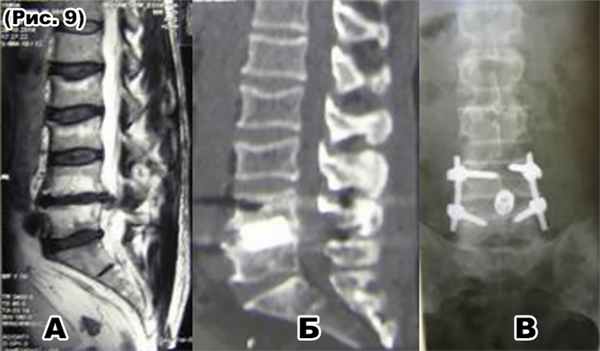

а) МРТ: парамедианная грыжа диска L4-L5 сегмента (стеноз п.к. 100%);

б) и в) КТ и R-граммы после декомпрессивно-стабилизирующей операции: трансфораминальнаядискэктомия, спондилодез кейджем с аутотрансплантатомL4-L5;

а) МРТ: дегенеративный стеноз позаоночного канала (90%) на уровне С4-С5-С6.

б),в) и г) КТ и R-граммыпосле декомпрессивно-стабилизирующей операции: ламинэктомия С4-С5-С6, задняя фиксации С3-С4-С5-С6-С7 позвонков и корпорэктомияС4-С5-С6 позвонков. Передний спондилодез мешем с аутотрансплантатом С3-С7 позвонков.